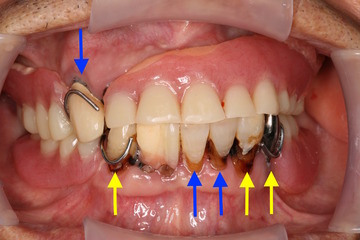

ケース NO.1 ⬆︎ 残した歯 ⬆︎ 抜いた歯

上が総入れ歯、下がレジリエンツテレスコープ義歯です。